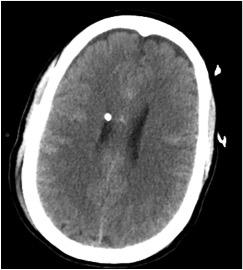

June 13, 2018 – Peter Chang, M.D., current neuroradiology fellow at UCSF and recently recruited co-director of the UCI Center for Artificial Intelligence in Diagnostic Medicine (CAIDM), is the honorary recipient of the Cornelius G. Dyke Memorial Award. The award was given by the American Society of Neuroradiology (ASNR) for Chang’s work in developing a customized deep learning system with over 97 percent accuracy in near real-time detection of hemorrhage on non-contrast computed tomography (NCCT) exam of the head.

The research, which was sponsored by Canon Medical Systems USA Inc., involved algorithm development on over 10,000 NCCT studies and included both detection and quantification of intraparenchymal, epidural/subdural and subarachnoid hemorrhages. Co-investigator Daniel Chow, who will join Chang as co-director at the CAIDM, explained that a tool such as this “may be implemented either as a triage system to assist radiologists in identifying high-priority exams for interpretation and/or as a method for rapid quantification of ICH volume, overall expediting triage of patient care and offering more detailed information to guide clinical decision making.”